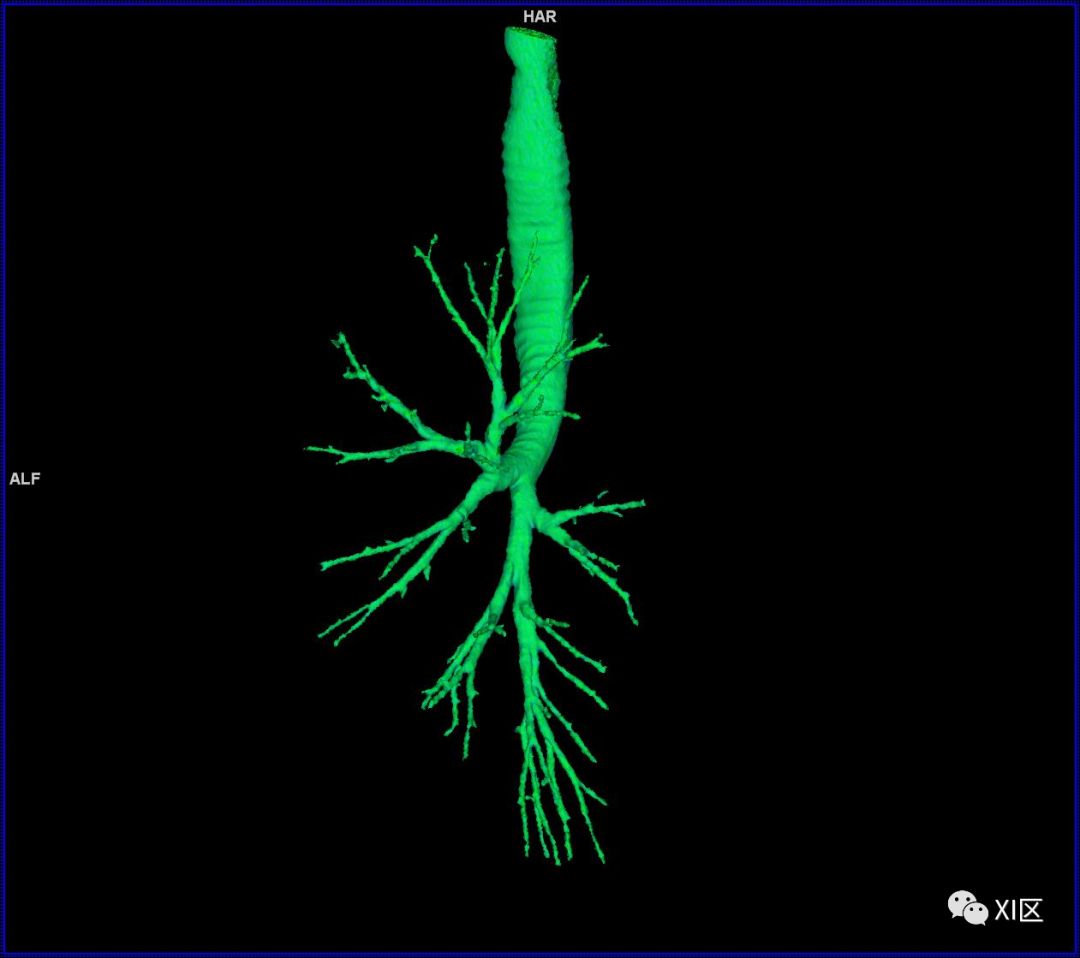

气管树

气管树与左右肺的关系

气管支气管形如树状,因此也称气管支气管树。